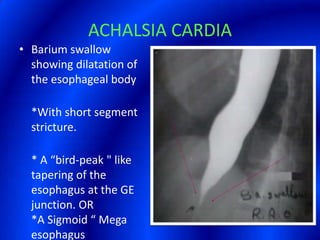

This document provides information about a barium swallow procedure. It begins with an introduction and overview of the embryology and anatomy of the pharynx and esophagus. It then describes the procedure itself, including preparation, technique, views obtained, and indications. Specific conditions that may be examined include pharyngeal and esophageal webs, foreign body impaction, scleroderma, dysphagia, mediastinal masses, and carcinoma. Diagrams are provided to illustrate normal anatomy and various pathological findings.